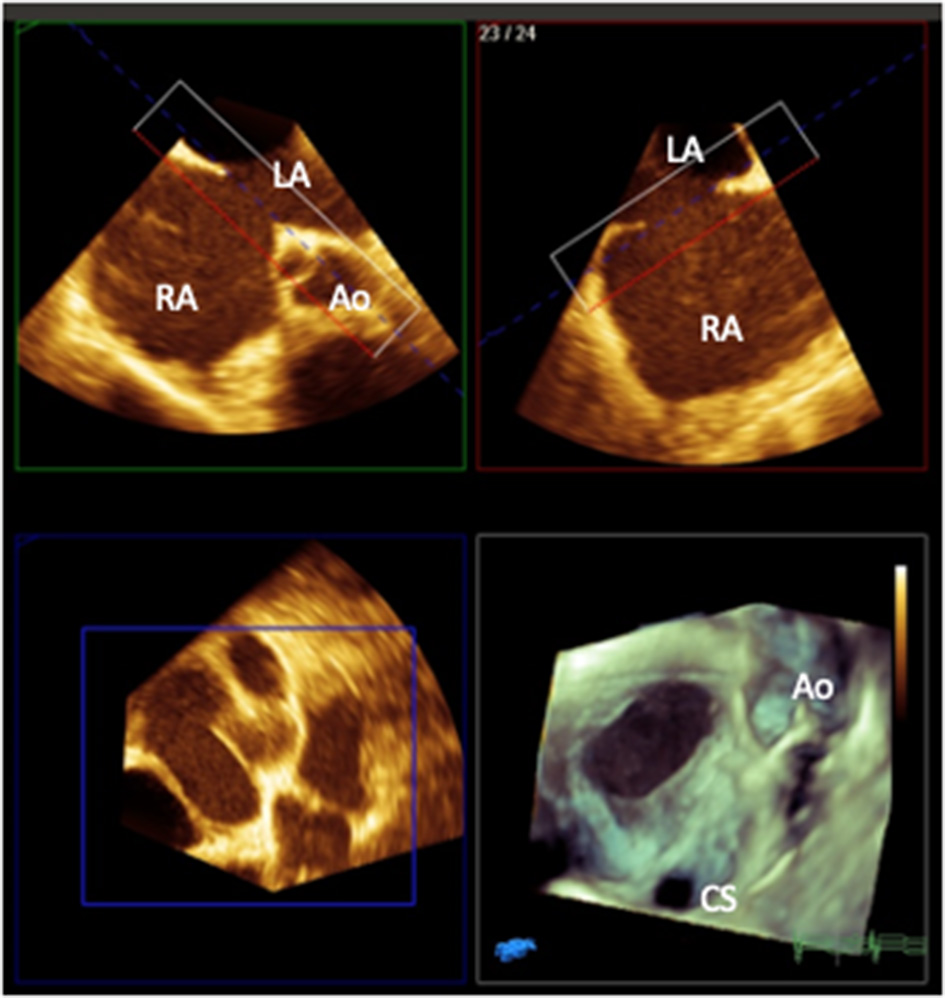

Three-dimensional echocardiography can further enhance visualization of ASDs particularly in the setting of complex or multiple defects (7) (Figure 1). Where there is a concern about the presence of concurrent anomalous pulmonary venous drainage which may need surgical intervention instead, TOE can be helpful, but 3D imaging with CT or CMR is more definitive. In rare occasions, CT is required for coronary imaging in the presence of a retroaortic circumflex coronary artery which may preclude device closure of an ASD (42).

Figure 1

3D multiplanar reformat and rendered image (bottom right) of a transesophageal image of a secundum atrial septal defect with a deficient aortic rim as viewed from the right atrial aspect (Ao, aorta; CS, coronary sinus; RA, right atrium; LA, left atrium). Image courtesy of Alexandra Savis, Evelina London Children's Hospital.